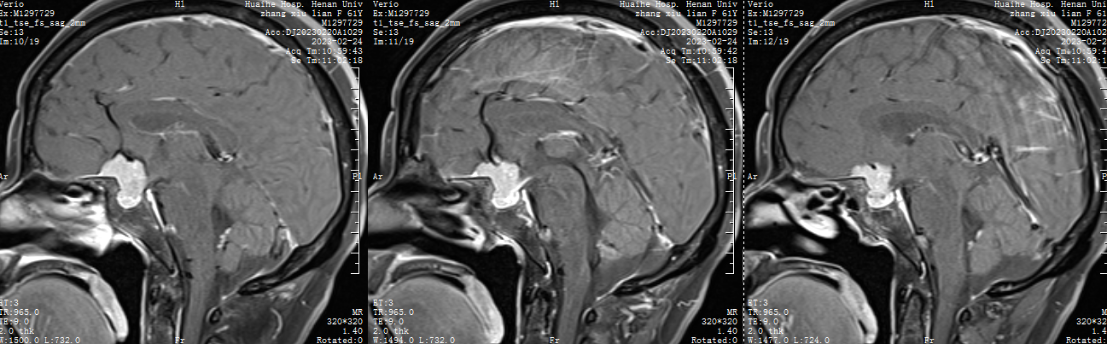

1.患者张XX,女,61岁,以“头晕2天”为主诉入院。

二 术前检查及会诊

自近蝶窦前壁处向左侧推挤鼻中隔,离断筛骨垂直板,咬除部分近蝶窦处骨性鼻中隔,分离双侧鼻粘膜显露蝶窦前壁,自蝶窦开口上方做沿鼻中隔做粘膜瓣备用,末端到中鼻甲位置,将粘膜瓣压向下鼻道,高速磨钻磨除蝶窦下壁骨质,鞍结节骨质。术中视神经管清晰可见,给予保护,海绵间窦出血给予流体明胶+凝血酶止血;等离子刀一边止血一边切开硬脑膜见白色肿瘤质韧,边界清晰,大脑前动脉分支粘连于肿瘤表面,给予小心分离,以刮圈,咬切钳等小心清除肿瘤组织;内镜下将肿瘤完整切除;取右侧大腿皮下脂肪及阔筋膜备用,以人工硬膜修补和明胶海绵封闭鞍底硬膜,将脂肪放置于切口,并缝合于鞍底硬脑膜上固定铺平,阔筋膜覆盖于脂肪外边,蝶窦内充填明胶海绵止血,鼻粘膜瓣覆盖于蝶窦;碘仿纱条填塞鼻腔;护士清点棉条、器械、纱布无误,撤出鼻镜。

鞍结节脑膜瘤(tuberculumsellaemeningioma TSMs)仅占颅内脑膜瘤的4%~10%。鞍结节脑膜瘤沿脑膜向周围生长,向前可达眶尖,向后可达斜坡及小脑幕,向外沿中颅窝底扩展,向内可累及鞍内垂体腺。常最早侵犯视神经,多以视力障碍为首发症状,产生颅高压为引起头痛、恶心、呕吐,侵犯垂体会出现垂体功能障碍相应症状。

内镜经鼻入路尤其适合3cm以下的中小型TSMs,但是当肿瘤体积更大或者呈分叶状时,本人喜欢采用扩大 翼点入路 ,而双额入路完全没有必要。

本例患者术前做了充分的讨论和准备,术后恢复良好。